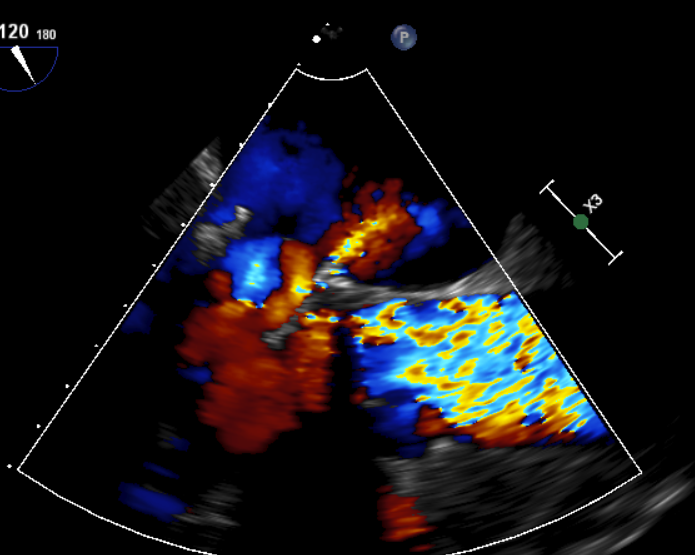

术中影像监护与评估(DSA&TEE)

过瓣流增快,呈“五彩状”

CDFI提示过瓣血流通畅

CDFI示少量瓣周漏

收缩期未见瓣周漏

左房内未见对比剂显影